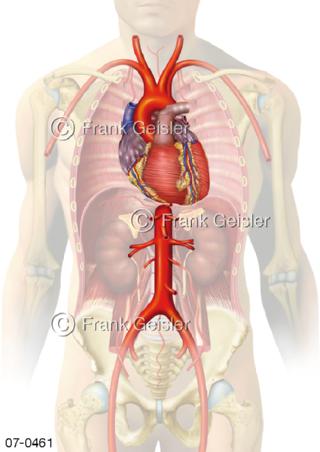

Bildergalerie Herz, Blutkreislauf

Bilder zu Herz, ein muskuläres Hohlorgan, das den menschlichen Körper durch rhythmische Kontraktionen mit Blut versorgt und dadurch die Durchblutung der Organe sichert, das Kreislaufsystem zeigt den Transport von arteriellem sowie venösem Blut durch das kardiovaskuläre System (Herz-Kreislauf-System), bestehend aus Blutgefäßen, Lymphgefäßen und dem Herz